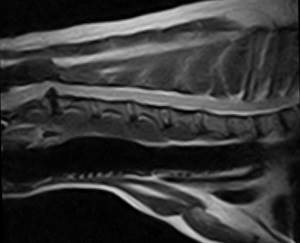

Окончательный диагноз миеломаляция может быть установлен с помощью рентгеноконтрастного исследования спинного мозга (миелографии) или МРТ соответствующего отдела спинного мозга, а также при патологоанатомическом вскрытии. В ряде случаев миеломаляция может быть установлена исходя из клинических симптомов.